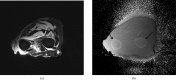

A variety of techniques are now available to directly or indirectly detect signal from tissues, fluids and materials that have short, ultrashort or supershort T₂ or T₂* components. There are also methods of developing image contrast between tissues and fluids in the short T₂ or T₂* range that can provide visualisation of anatomy, which has not been previously seen with MRI. Magnetisation transfer methods can now be applied to previously invisible tissues, providing indirect access to supershort T₂ components. Particular methods have been developed to target susceptibility effects and quantify them after correcting for anatomical distortion. Specific methods have also been developed to image the effects of magnetic iron oxide particles with positive contrast. Major advances have been made in techniques designed to correct for loss of signal and gross image distortion near metal. These methods are likely to substantially increase the range of application for MRI.